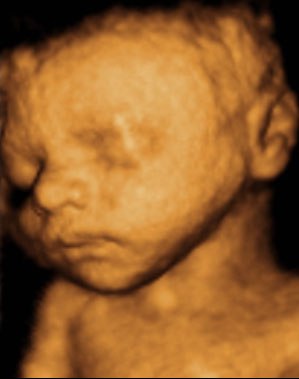

Kan da lige sætte et par billeder ind fra i mandags, hvor jeg var 27+5 uger henne, så du kan se kvaliteten

Vedhæftede fotos (klik for at se i fuld størrelse)